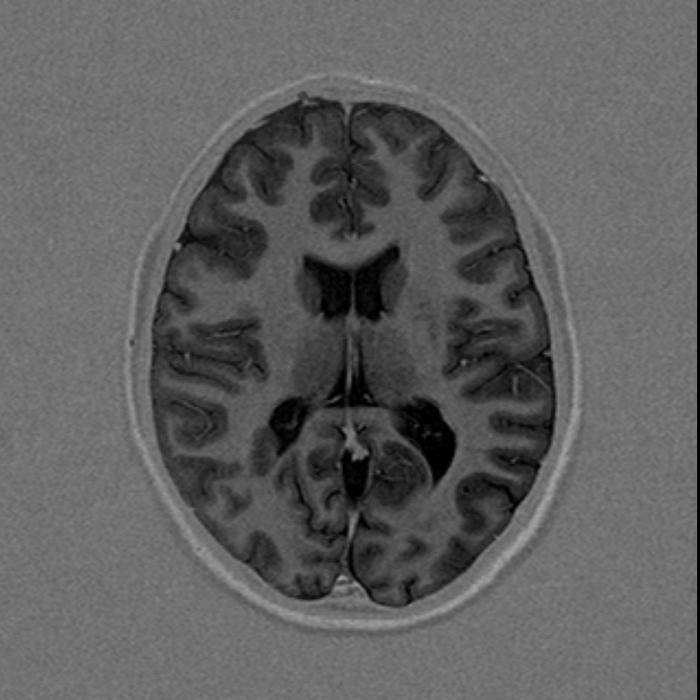

По итогам исследования, на снимках суб- и супратенториальных областей мозга выявлены единичные (в количестве трех) перивентрикулярные очаги: справа на уровне задних рогов боковых желудочков размером до 6х3 мм, слева до 5х3 мм и сверху правого бокового желудочка до 5 мм, без следов перифокального отека (они слабо гиперинтенсивные на Т2 FLAIR и Т2 ВИ, изоинтенсивные на Т1 ВИ и DWI). Других очаговых изменений в веществах больших полушарий, ствола, мозолистого тела и мозжечка не обнаружено.

В проекции заднего рога правого бокового желудочка обнаружен участок гетеротопии серого вещества размером 18х12 мм, который поджимает задний рог бокового желудочка. Заключение: МРТ-картина узловой гетеротопии в области правого бокового желудочка.

МРТ головного мозга (март 2018):

МРТ для диагностики перивентрикулярного лейкоареоза головного мозга